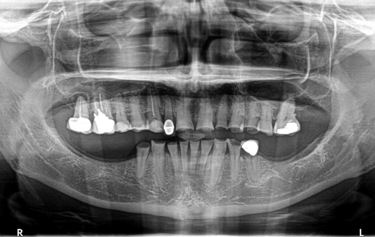

Panoramic radiograph (Fig. 3) showed radiolucency suggestive of chronic periapical pathology on both her upper right remaining molar teeth, her upper right canine tooth, and her lower left second premolar tooth. The root-treated upper right molar teeth were considered to be of a poor standard, with only partial obturation of the canals. Clinically there was an advanced area of dental decay undermining the distal aspect of the crown on the lower left second premolar tooth and caries noted on the upper right molar teeth.

Figure 3: Panoramic radiograph